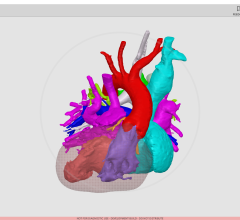

MRI is a vital imaging tool for the evaluation, assessment and management of the liver. CADstream’s liver application features include automated 3D image registration, segmentation (including whole organ, Couinaud-segments and lesion segmentation), kinetic and diffusion-weighted imaging analysis, patient monitoring comparisons and reporting. With CADstream, clinicians have a solution to automate analysis and standardize interpretation, ultimately achieving higher quality imaging studies, lower costs for radiology practices and improved communication for physicians and patients. Merge CAD will also showcase the latest in CADstream’s breast and prostate applications at RSNA 2009.